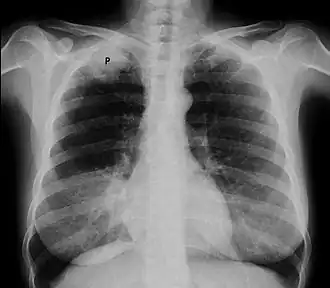

- Radiographie thoracique montrant une opacité de l'apex[1]